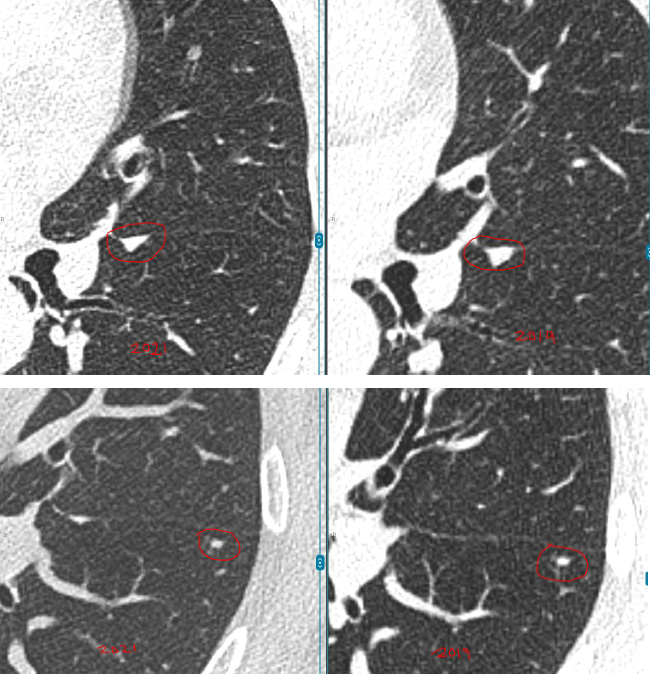

每年复查,她都紧张得睡不着。好在3个结节都一直很“老实”,没变大。可四年后的一次CT复查,让她的心又提了起来:

左肺结节无变化,但右肺的4mm结节密度增高了,还又新添了一颗3mm的磨玻璃结节。

教授指出,右肺那颗4mm的磨玻璃结节虽然密度略有增加,但变化非常小,还不足以判断为恶化。

而左肺的两枚实性结节稳定了三年多,良性可能性超过99%。另外舌叶可见线状影,较前稳定,符合炎性、瘢痕特征。

至于新出现的那颗3mm磨玻璃结节,教授认为它也很“温和”,更像是一种暂时的炎性反应,有可能过段时间就自行消失了。

“这些结节都太小,目前还不到该切的程度,继续观察很安全。”L教授说。他建议孙女士每年复查一次CT,不需要手术、不用活检。